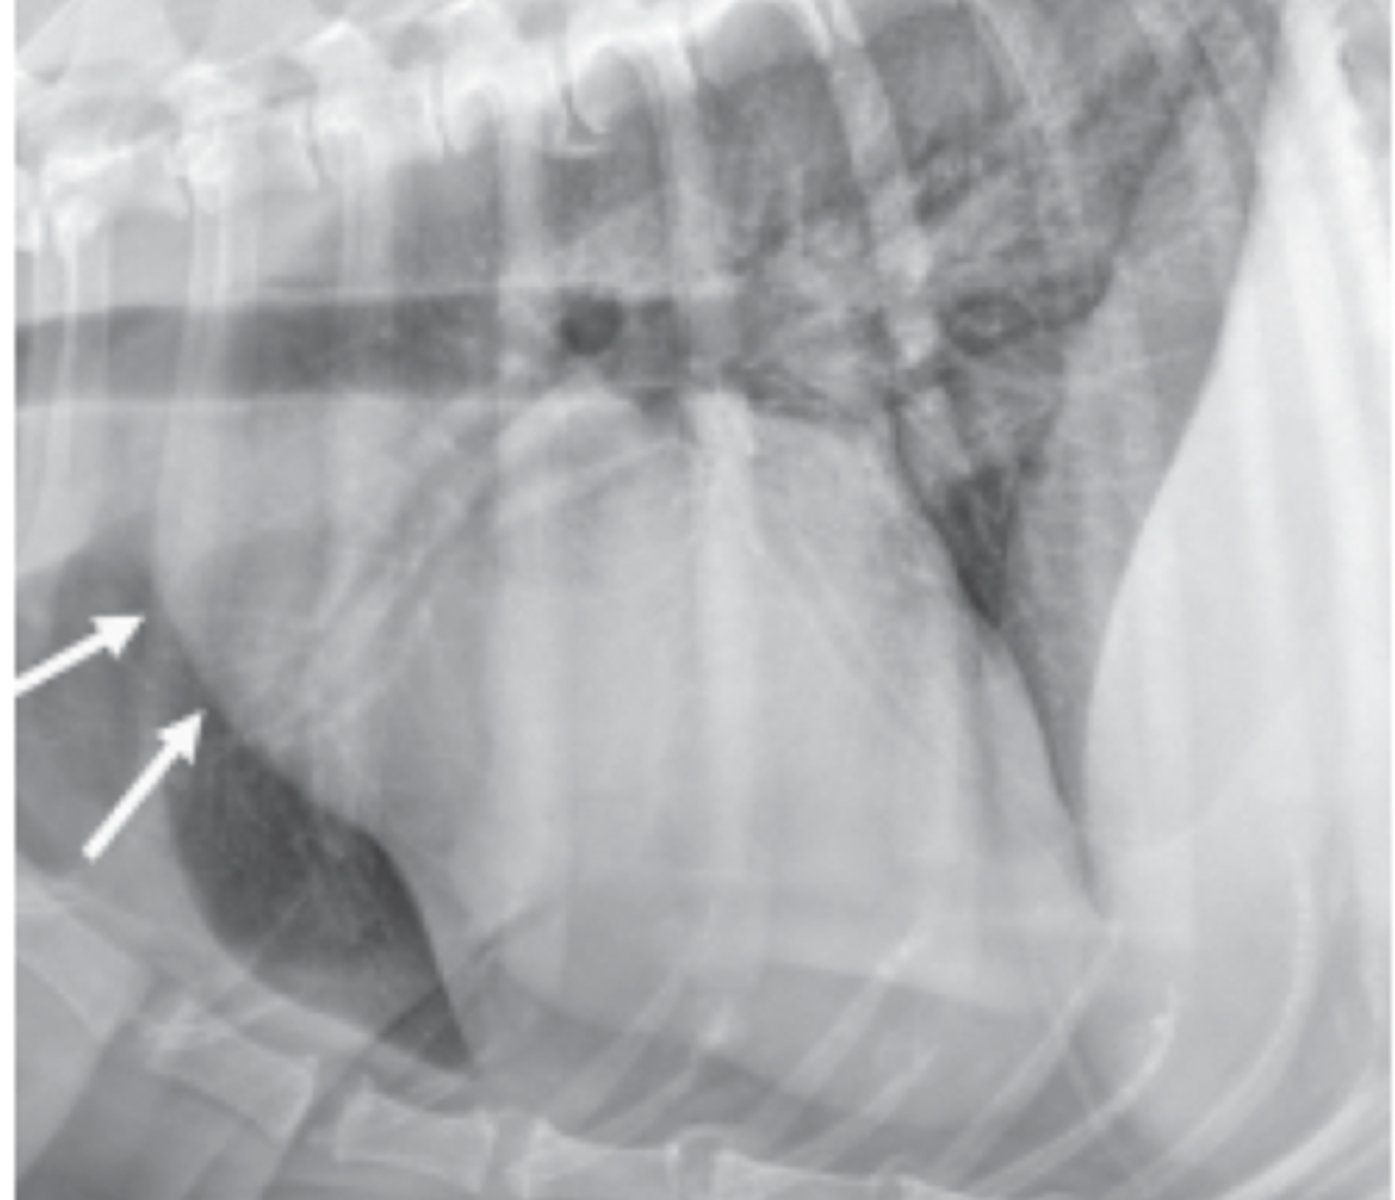

dilatación-torsión gástrica

patología: